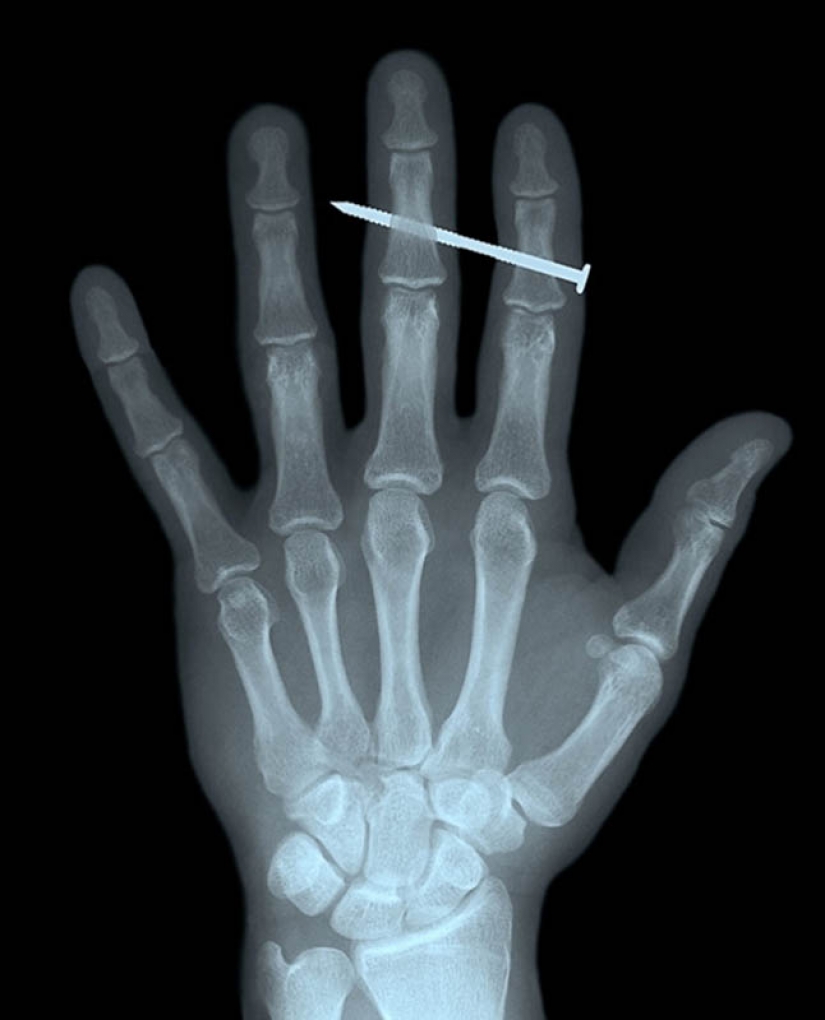

4. The nail in the bones of the index and middle fingers of adult men.